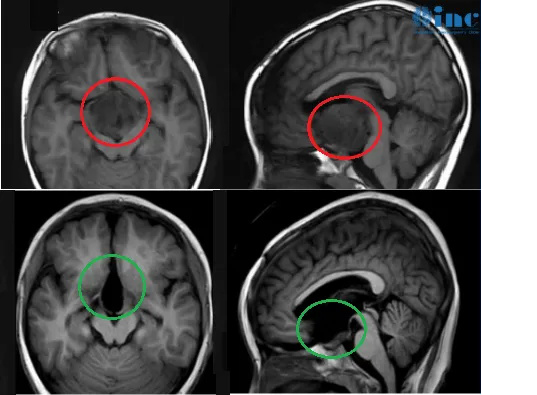

康康术前术后影像对比